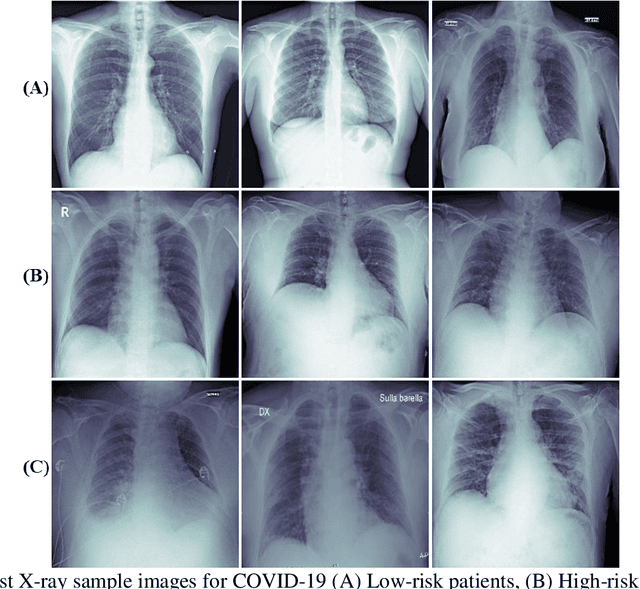

Abstract:Fast and accurate detection of the disease can significantly help in reducing the strain on the healthcare facility of any country to reduce the mortality during any pandemic. The goal of this work is to create a multimodal system using a novel machine learning framework that uses both Chest X-ray (CXR) images and clinical data to predict severity in COVID-19 patients. In addition, the study presents a nomogram-based scoring technique for predicting the likelihood of death in high-risk patients. This study uses 25 biomarkers and CXR images in predicting the risk in 930 COVID-19 patients admitted during the first wave of COVID-19 (March-June 2020) in Italy. The proposed multimodal stacking technique produced the precision, sensitivity, and F1-score, of 89.03%, 90.44%, and 89.03%, respectively to identify low or high-risk patients. This multimodal approach improved the accuracy by 6% in comparison to the CXR image or clinical data alone. Finally, nomogram scoring system using multivariate logistic regression -- was used to stratify the mortality risk among the high-risk patients identified in the first stage. Lactate Dehydrogenase (LDH), O2 percentage, White Blood Cells (WBC) Count, Age, and C-reactive protein (CRP) were identified as useful predictor using random forest feature selection model. Five predictors parameters and a CXR image based nomogram score was developed for quantifying the probability of death and categorizing them into two risk groups: survived (<50%), and death (>=50%), respectively. The multi-modal technique was able to predict the death probability of high-risk patients with an F1 score of 92.88 %. The area under the curves for the development and validation cohorts are 0.981 and 0.939, respectively.